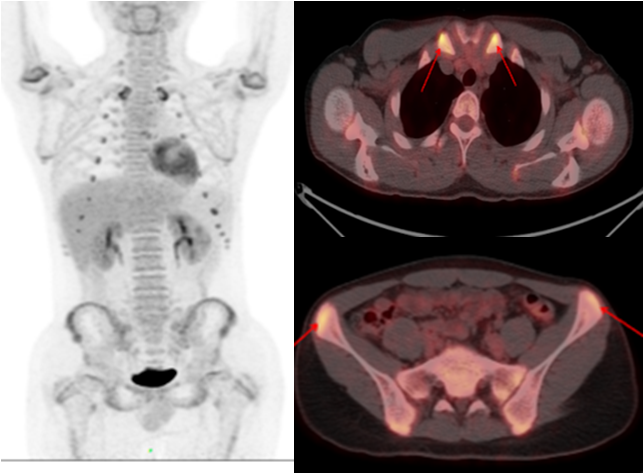

PET/CT是高端的分子影像診斷設備,被譽為醫學影像學”皇冠上的明珠”。PET/CT所用的示蹤劑18F-FDG是葡萄糖類似物,當機體因腫瘤、感染與炎癥而導致FUO時,腫瘤細胞和炎癥細胞往往高表達葡萄糖轉運蛋白(GLUT),導致18F-FDG在病灶內大量聚集,從而被PET/CT從功能代謝水平精準定位,為進一步輔助檢查和診斷提供有力的方向和依據。

少年男性,間斷發熱半年,一直未找到原因。PET/CT 顯示多處關節、軟骨高代謝灶,最終診斷為復發性多軟骨炎導致的不明原因發熱,經指導后臨床治療效果良好。